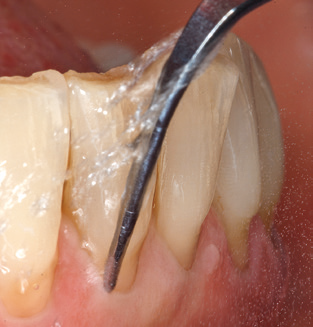

Die gute Ausleuchtung des Arbeitsfeldes stellt eine wesentliche Erleichterung dar. Bei dem von den Autoren genutzten System ist dies gelungen, indem ein 5­facher LED­Ring in das Handstück integriert wurde. Natürlich werden für dieses System unterschiedliche Arbeitsspitzen für die jeweiligen Indikationsbereiche angeboten. Eine gerade, universell einsetzbare Spitze ist das Basisinstrument zur maschinellen Instrumentierung natürlicher Zähne (Abb. 5a und b). Für schwer zugängliche Bereiche im Seitenzahnbereich werden gebogene Spitzen angeboten, die auch einen Zugang zu freiliegenden Furkationen ermöglichen (Abb. 6).

Abb. 4: Für das Sondieren an dentalen Implantaten sind biegsame, millimeterskalierte Sonden empfehlenswert (z.B. Colorvue Kit PCV11KIT6, Hu-Friedy). – Abb. 5a und b: Eine gerade Arbeitsspitze (1P, W&H Dentalwerk Bürmoos GmbH) ist universell für die Instrumentierung natürlicher Zähne geeignet. – Abb. 6: Für die Bearbeitung schwer zugänglicher Bereiche der Zahn- und Wurzeloberflächen (z.B. Furkationen) bieten sich gebogene Arbeitsspitzen (3Pr/3Pl, W&H Dentalwerk Bürmoos GmbH) an. – Abb. 7: Die spitz zulaufende sechseckige Implantatreinigungsspitze (1I, W&H Dentalwerk Bürmoos GmbH) ermöglicht eine atraumatische und effiziente Reinigung der Kronen- und Abutmentoberflächen. – Abb. 8: Für die manuelle Instrumentierung der Implantatoberflächen sind Titan- oder Carbonküretten geeignet.